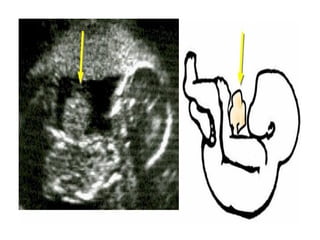

• Prenatal ultrasonography often identifies the

gastroschisis

Exams and Tests •Physical examination of the infant is sufficient for the health care provider to diagnose gastroschisis • The mother may have shown signs indicating excessive amniotic fluid ( polyhydramnios) • Prenatal ultrasonography often identifies the gastroschisis